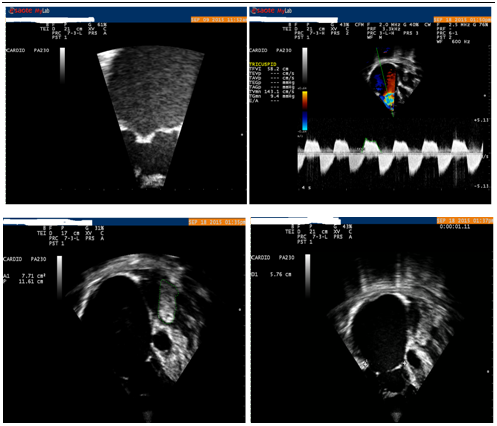

Dilated inferior vena cava-18mm, dilated right atrium 87 *63 mm with an area of 51,17cm2 and a circumference of 27 mm, the anterior and posterior leaflets were calcified and fused (Figure 1A), giving a severe stenosis with a peak gradient of 22,5 mmHg, the mean gradient was 9,9 mmHg, and pressure half time of 218 ms (Figure 1B). The tricuspid annulus was 57 mm (Figure 1D). The color continuous Doppler through the tricuspid valve gives also a mild regurgitation with a vena contracta-8 mm, we could see also the retraction of the subvalvular apparatus. The right ventricle is dilated but the systolic function was not compromised with a transannular annular plane systolic excursion-21mm. There was right ventricular systolic overload.

Figure 1 The echocardiogram of the patient.

A: Zoomed image of the fusion of tricuspid valve leaflets.

B: Continuous Doppler through the tricuspid valve showing a peak gradient of 22, 5 mmHg, the mean gradient was 9,9 mmHg, and pressure half time of 218 ms.

C: At the apex of the left atrium a mass having a circumference of 11, 1 mm, with a long axis of 44 mm and a short axis-18,5 mm.

D: Dilated right atrium 87 *63 mm with an area of 51, 17 cm2 and a circumference of 27 mm, the tricuspid annulus having a dimension of 57 mm.

The left atrium 69 *48 mm with an area of 26,7cm2 and a circumference of 21mm is having at the apex near the entrance of the inferior pulmonary veins a mass homogenous well organised looking like a myxoma having a circumference of 11,1 mm, with a long axis of 44 mm and a short axis-18,5 mm (Figure 1C). The mitral leaflets are mildly calcified with good function. The annulus is not dilated, 29 mm. The left ventricle is not dilated with a paradoxal septum and acceptable systolic function.